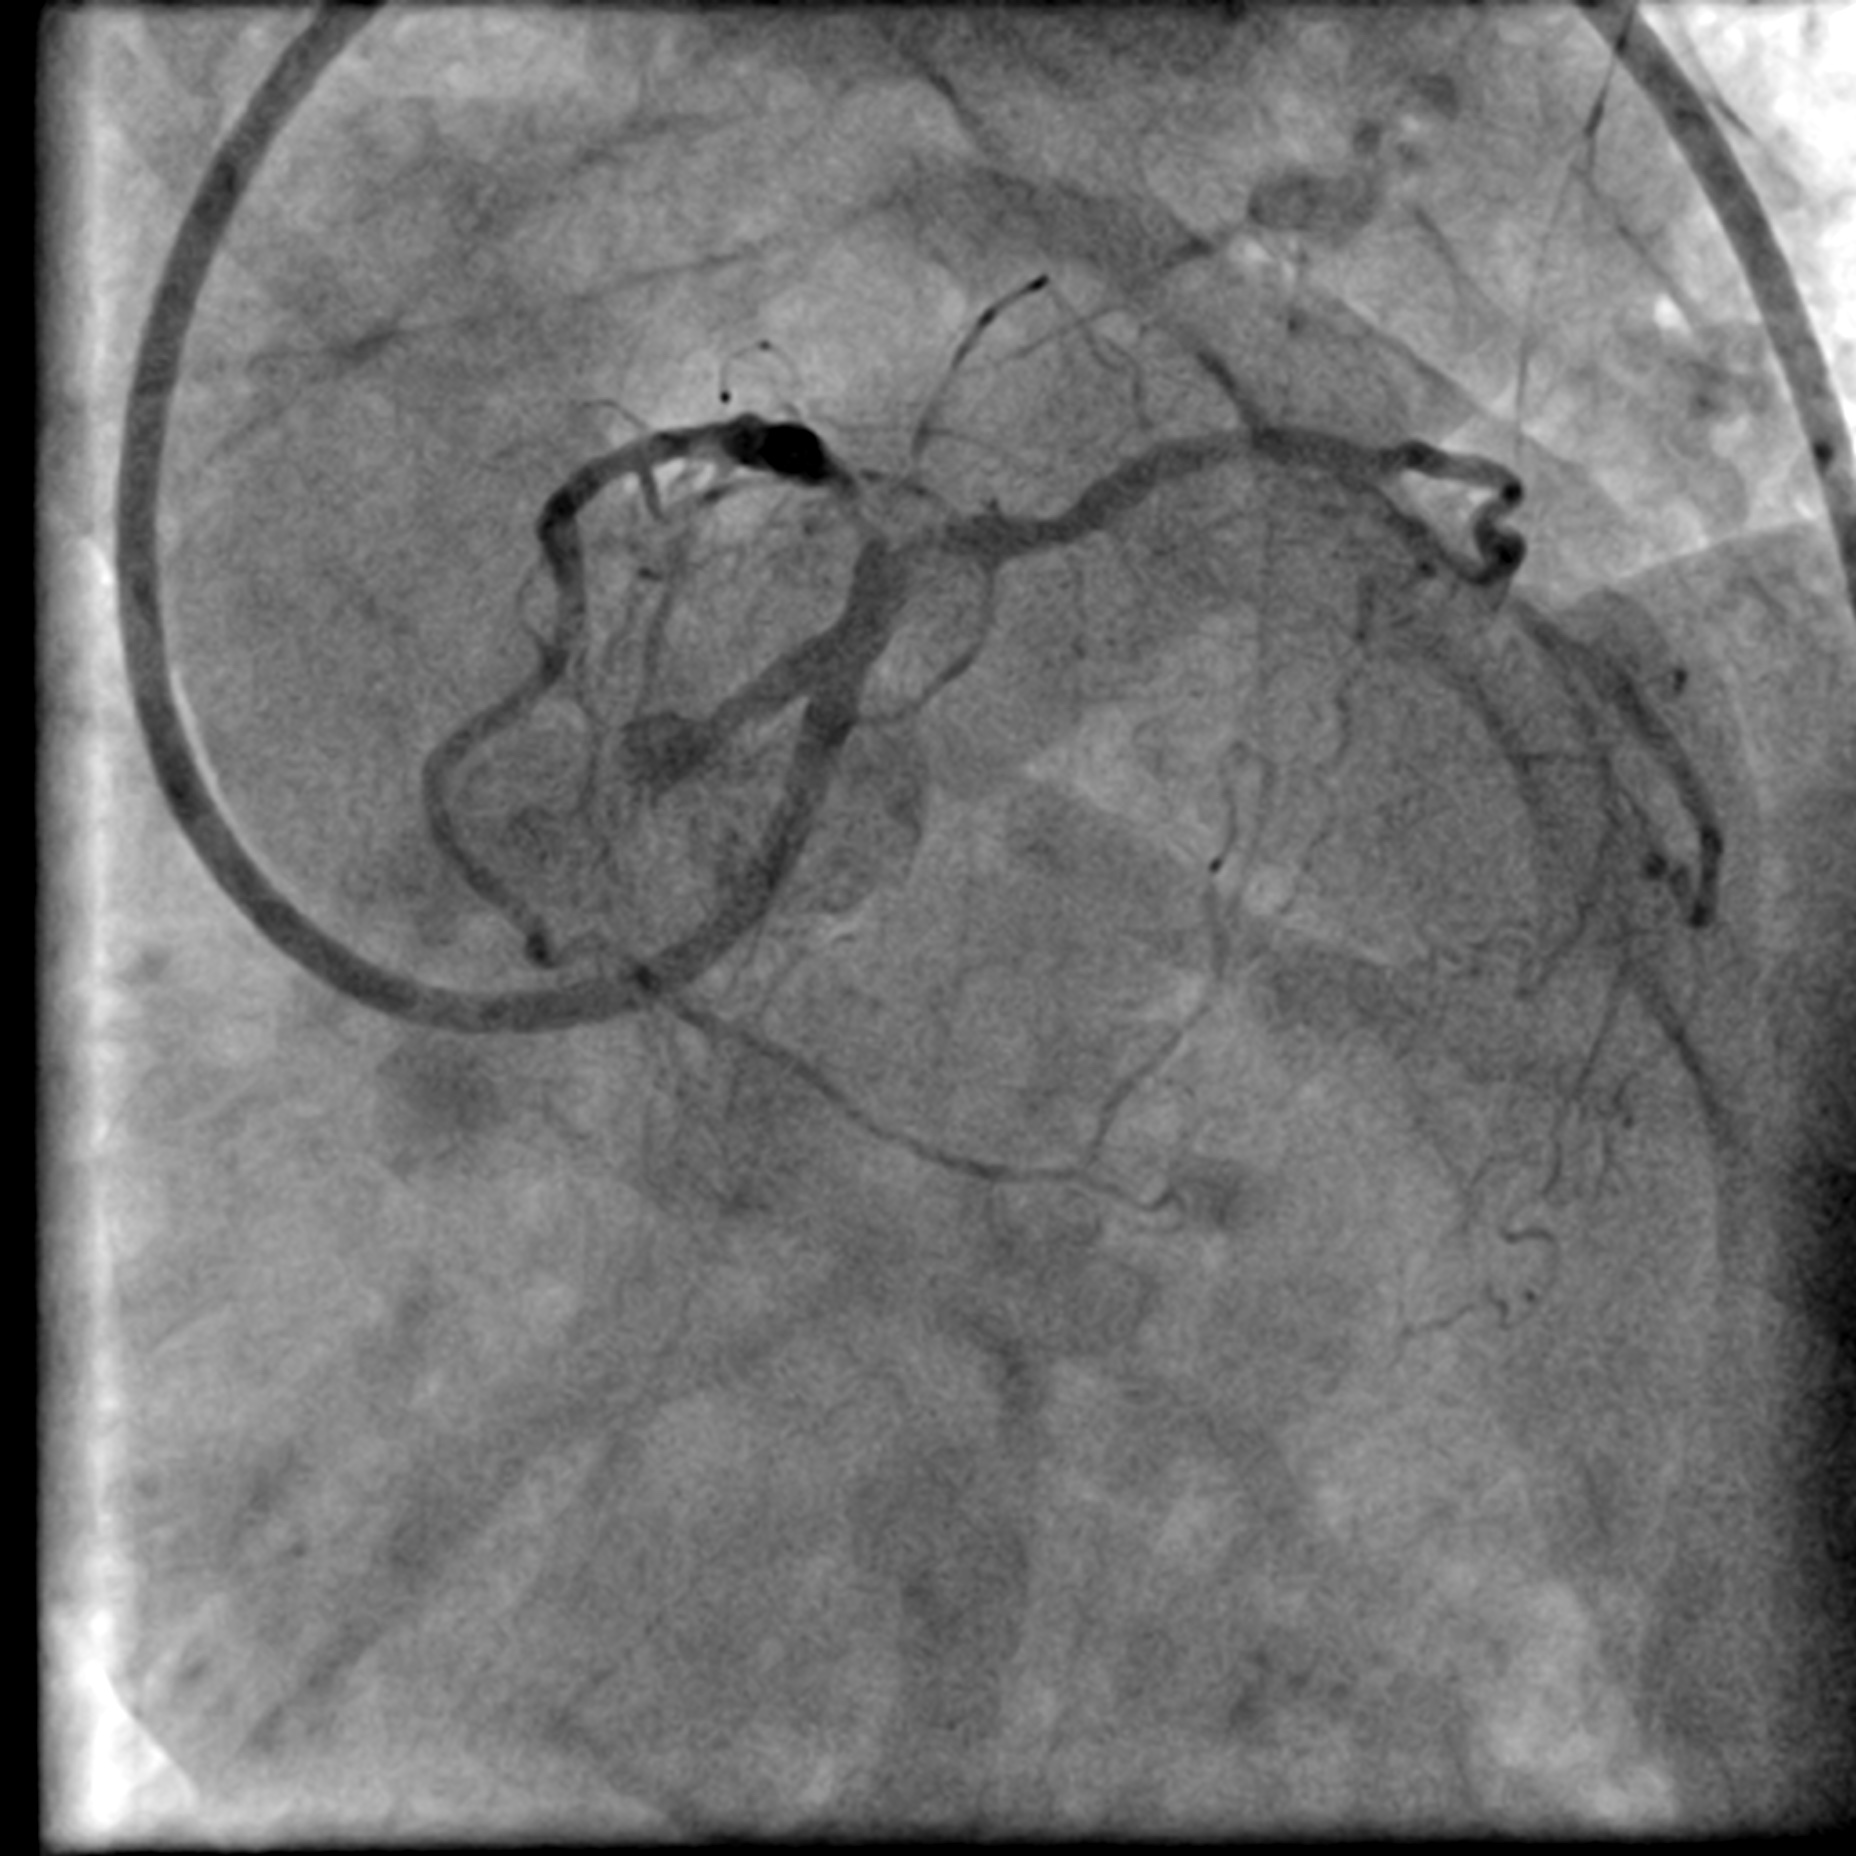

A LMS hybrid therapy was planned. A 7 Fr EBU 3.5 catheter was engaged to the LMS. Two workhorse wires were placed in the distal LAD and LCx. The LAD was pre-dilated with a 3.5 mm cutting balloon without facing significant difficulty. However, pre-dilatation of the LCx with a 3.5 mm cutting balloon was unsatisfactory due to the calcium nodule. This was overcome with lesion preparation using a 3.5 mm Lithix balloon. Adequate lesion preparation was confirmed with repeated angiography and IVUS assessment. The ostial LCx was treated with a 3.5 x 20 mm Drug-Coated Balloon (DCB), while the LMS-LAD segment was stented with a 4.0 x 22 mm Drug-Eluting Stent (DES). Proximal Optimization Technique (POT) was performed using a 4.5 mm NC balloon, and the stent in the LAD segment was post-dilated with a 4.0 mm NC balloon. Repeated angiography revealed a Type B dissection with a narrowed lumen in the LCx, necessitating stenting. The LCx was re-wired using a dual-lumen catheter from the inner frame of the LMS stent. The stent strut was opened with a 2.0 mm balloon and a 3.5 mm NC balloon. T-stenting of the ostial LCx was performed with a 3.0 x 26 mm DES, utilizing a balloon catheter in the LAD wire as a marker. The LCx stent was first post-dilated with a 3.5 mm NC balloon. Subsequently, the Kissing Balloon Technique (KBT) was performed with a 4.0 mm NC balloon in the LAD and a 3.5 mm NC balloon in the LCx. Finally, repeated POT was completed with a 4.5 mm NC balloon in the LMS.

Dissected LCx.mp4